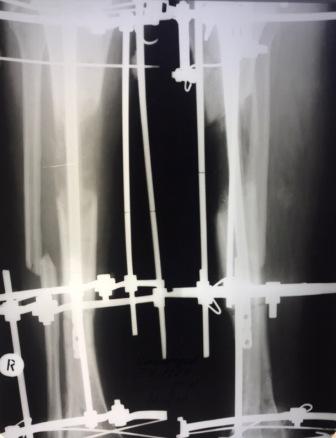

Когда демонтировать аппарат? Уважаемые коллеги, восстановили длину конечности у молодого пациента после острого укорочения после травмы. Восстанавливали на стержне, снимок прилагаю. Как рекомендуете поступить дальше, когда демонтировать аппарат, режим реабилитации после этого и т.д. Поделитесь опытом. Спасибо.

Снимок

Длину восстановили- отлично. Блокируйте и снимайте аппарат. Блокирование пока статически.

Михаил, спасибо, но смущает близость зоны перелома к блокирующим винтам - не более 2-3 см, не повлияет ли потенциальная нестабильность на регенерат?

Чесно говоря перелома не разглядел.

1. А что мешает блокировать в двух плоскостях, в конце концов поставить полерные винты.

2. Если есть сомнения, подождите, дайте нагрузку дозировано в аппарате.

Если линия перелома на 3 см выше верхушки гвоздя, боятся надо не за регенерат, а за риск периимплантного стрессового перелома при нагрузке. А гвоздик подлиннее нельзя поставить? Это бы решило все проблемы. И в путь. А так до убедительной консолидации перелома. Я его не углядел.

Согласен, блокировать данный гвоздь рискованно. Заменить на длинный и большего диаметра решит проблему, и аппарат можно демонтировать.